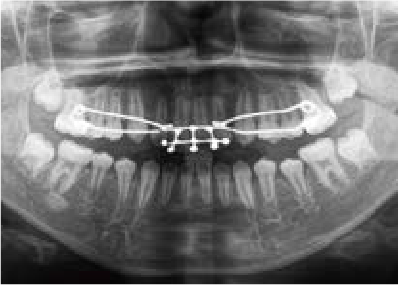

出っ歯

「本当に永久歯を抜かずに治るの?」半信半疑で相談に来られました

Mさん (矯正開始時:8歳)

Before

After

これから生えてくる永久歯のスペースがなく、歯が並ぶ余地がほとんどありませんでした。

さらに、上からあごの骨を見たところ、中央がくびれた“ひょうたん型”に変形しており、あごの成長にも偏りが見られました。

診断の結果、前歯の中心も少し左にずれており、特に犬歯が生えるスペースが足りない状態でした。

飲み込むときに下くちびるに力が入り、顔の左側にゆがみが出ている様子も確認できました。

治療を終えて

犬歯が歯ぐきの中に埋まっていたため、透明のマウスピース型装置で生えるスペースを作り正しい位置に導きました。もちろん抜歯せずに歯並びを整えることができました。お口の中がとても小さく、型どりの際にオエッとなる反応が強く、当時は装置を作るのが大変でした。しかし現在では3Dスキャナーと3Dプリンターを活用しスムーズに治療できます。

主訴・治療内容 「あごが小さいから、歯がきれいに並ばない」と他院で言われ永久歯を抜く矯正をすすめられていました。

本当に非抜歯で治療できるのか心配されていましたが、治療方法を丁寧にご説明し、お任せいただきました。

治療期間 5年

費用 550,000円(税込)